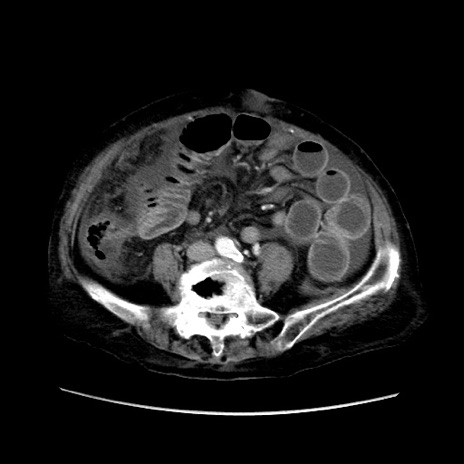

症例31(横断像)

【症例】80歳代 女性

【主訴】腹部膨満感

【現病歴】他院にて肝硬変にてフォロー中。1週間前から便秘、腹部膨満感、臍部腫瘤あり受診となる。

【既往歴】肝硬変

【身体所見】腹部膨隆あり、皮膚変化なし、疼痛なし。

【データ】WBC 4600、CRP 0.25